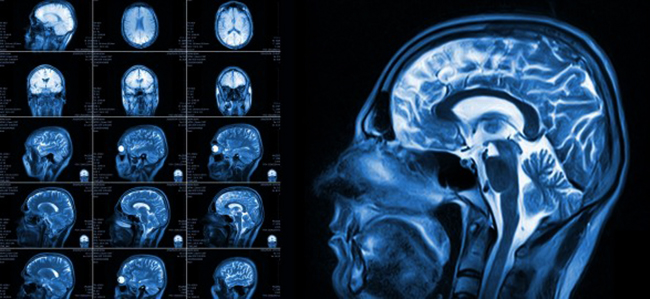

Магниторезонансная томография

С развитием технологий стал применяться и другой метод томографии, основанный на явлении ядерного магнитного резонанса. Основан он на взаимодействии вещества с магнитным полем. Магнитное поле обычного магнита слишком слабое, и с ним заметно взаимодействуют лишь некоторые магнитные вещества (называемые ферромагнетиками – железо, никель и некоторые другие). Прочие вещества с магнитным полем взаимодействуют очень слабо, и это взаимодействие совершенно не заметно. Однако, если взять очень мощное магнитное поле, то с помощью чувствительных детекторов можно уловить небольшие изменения, происходящие и в немагнитных веществах, своего рода «ответ». На этих явлениях и основана магниторезонансная томография.

Как правило, детекторы улавливают магнитный резонанс атомов водорода, входящих в состав жидкостей организма, таким образом, магниторезонансная томография позволяет хорошо рассмотреть структуру мягких тканей организма, которые содержат много жидкости. Структура твердых тканей, содержащих мало жидкости, видна гораздо хуже.

Вред магниторезонансной томографии

Как было сказано выше, магниторезонансная томография основана на детектировании «отклика» тканей организма, помещенных в сильное магнитное поле. Поскольку человеческий организм состоит из тканей, очень слабовзаимодействующих с магнитным полем, в первом приближении можно считать, что магниторезонансная томография является безвредной.

Однако, следует учесть, что магнитное поле внутри томографа во много раз выше обычного земного магнитного поля.

Для справки: обычное магнитное поле Земли имеет интенсивность около 0,05 мТл. Даже в местах земных магнитных аномалий оно не превышает 0,3 мТл. Это магнитные поля, с которыми «сталкивалась» эволюция, приспосабливая живые существа к условиям обитания.

Но, даже сила обычного бытового магнита из магнитных защелок гораздо выше, и составляет около 5 мТл. А в МРТ-томографе сила магнитного поля равна 1000, 1500 и даже 3000 мТл!

Научные исследования воздействия таких магнитных полей на живые организмы не выявили достоверных негативных результатов. Ставились даже опыты над живыми существами (мышами и лягушками) в магнитных полях 15000 мТл, при таких исключительно сильных магнитных полях обычное вещество уже начинает реагировать на магнитное поле, подопытная лягушка начинает «парить», не касаясь поверхности. Однако, после опыта – она вполне неплохо себя чувствует.

Таким образом, можно утверждать, что прямого явного вреда от МРТ на организм человека нет.

Из всего сказанного следует, что МРТ-томография является на сегодняшний день значительно более безопасным методом, чем КТ-томография. Однако, решение о выборе того или иного метода должен принимать лечащий врач.

Дело в том, что, как было указано выше, в описаниях методик, КТ-томография позволяет хорошо различить структуру твердых тканей организма, и гораздо хуже отображает состояние мягких. МРТ же, гораздо лучше подходит для исследования мягких тканей, и меньше подходит для исследования твердых.

В случае же примерно эквивалентных показаний, когда с точки зрения лечащего врача пациенту одинаково может подойти как КТ, так и МРТ, следует выбрать МРТ, как менее опасный метод, не связанный с ионизирующими излучениями.